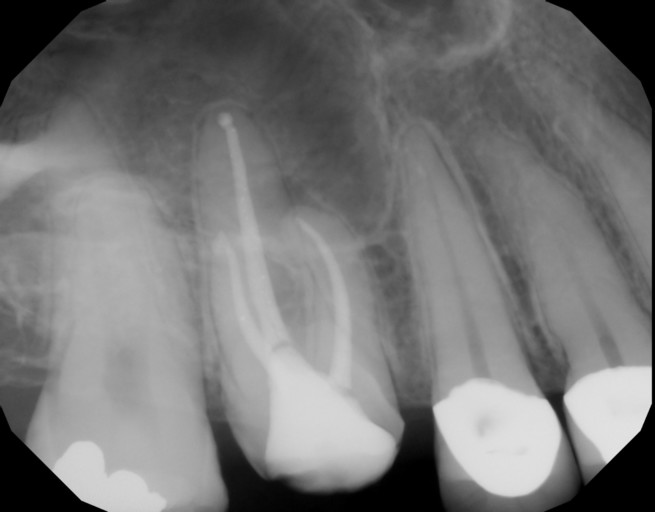

Hello! I found you on ask a dentist and I’m hoping you can ease a worried mind. I had a root canal on tooth 12 the beginning of February. Apparently the tooth had a tiny old filling that leaked. No infection but tooth was dying. Following root canal I had extreme pain. RC was redone in March, pain continued. This past Friday the Endodontist performed an Apicoectomy. There was small infection above the tooth root and some swelling. I am healing well. Main source of ache is in my chipmunk cheeks. Gums are tender but feel good. No swelling like there was about tooth root any longer. my question is, is it normal for the Apico tooth to feel different right now? Even a bit tender to pressure? It’s not necessarily painful but a definite “feeling” and tender. I thought that if the tooth had no root it would no longer feel sensation. Just sitting here worrying about this poor tooth and hoping someone has some thoughts on this. And I need to stop “testing” it! Thank you so much! I’m so insanely worried about this little tooth.